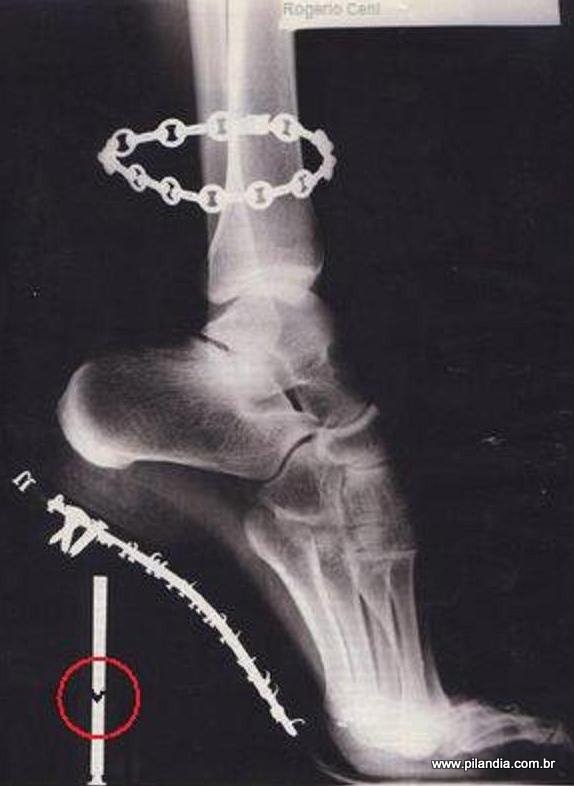

* Sapatos: é importante manter os quatro pontos de apoio no chão como descrito anteriormente. Dessa forma é importante evitar sapatos de bico fino, que diminuem a largura do pé, estimulando joanetes e inflamações dos pontos de maior pressão. Para saber se o seu pé está bem acomodado você pode fazer um desenho sobre uma folha de papel ao redor do sapato e depois ao redor do seu pé descalço. O salto não deve impedir que o calcanhar tenha dois pontos de apoio no chão. O salto fino, não permite esse apoio e acaba criando uma pressão sobre a parte anterior dos pés.

O salto muito alto e fino torna impossível tocar o chão com o calcanhar, como é o indicado. O uso constante de salto alto propicia a formação de calos, processo inflamatórios, desenvolvimento de joanete e encurtamento da musculatura posterior da perna (panturrilha) que tem o objetivo de impulsionar o corpo para frente quando andamos e segurar a perna na posição vertical quando paramos. Mulheres que utilizam diariamente salto alto chegam ao ponto de não conseguir mais colocar os pés no chão e utilizar tênis ou chinelo.